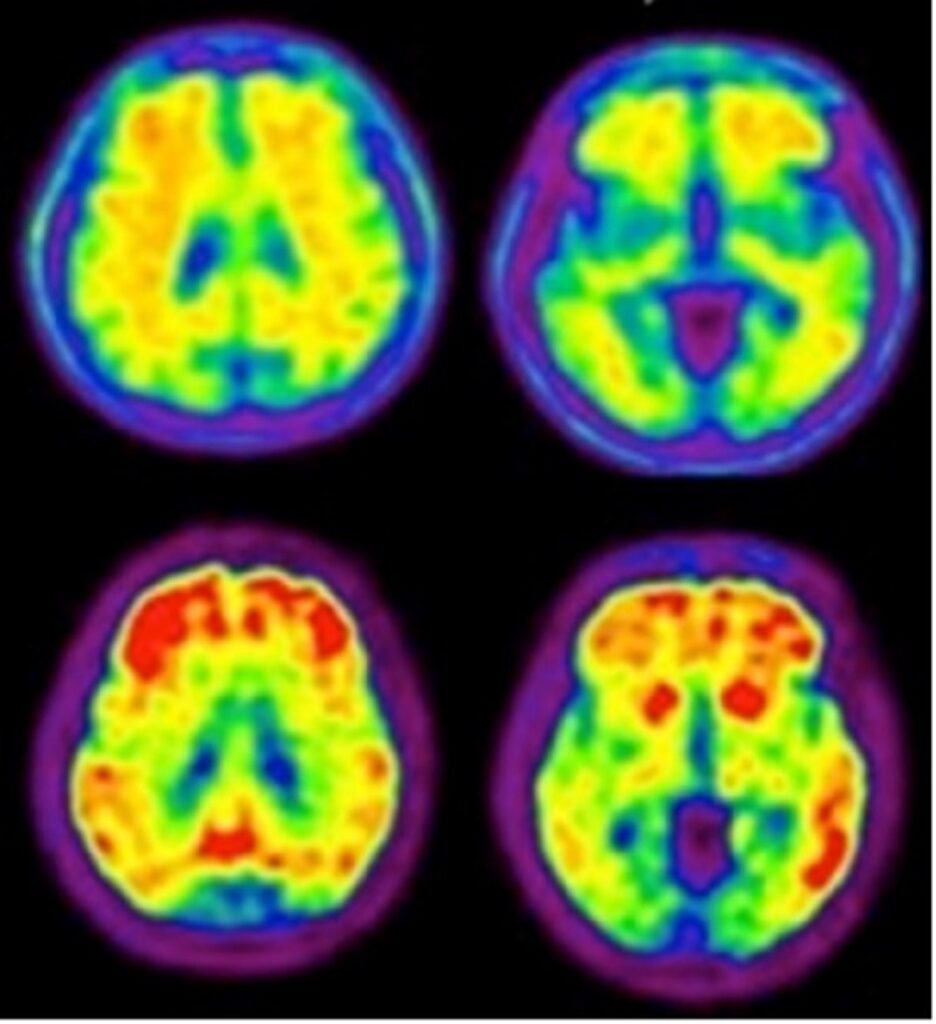

Figure 1: Same patient comparison of an FDA-approved 18F-Aβ tracer (top row) to 18F-NAV4694 (bottom row) (Krishnadas 2021).